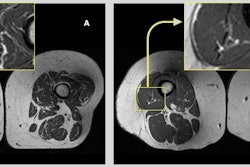

"MRI is comparable to CT in accurately measuring adipose tissue deposits and intermuscular adipose tissue, and muscle volume," the team explained. "Additionally, MRI estimates the fat fraction (expressed as percentage) of different organs as liver, muscle, pancreas or bone marrow tissue. Moreover, because of its high accuracy and reliability, MRI can be used to measure the relatively small changes that may occur during longitudinal and interventional studies (e.g., lifestyle or pharmacological interventions)."